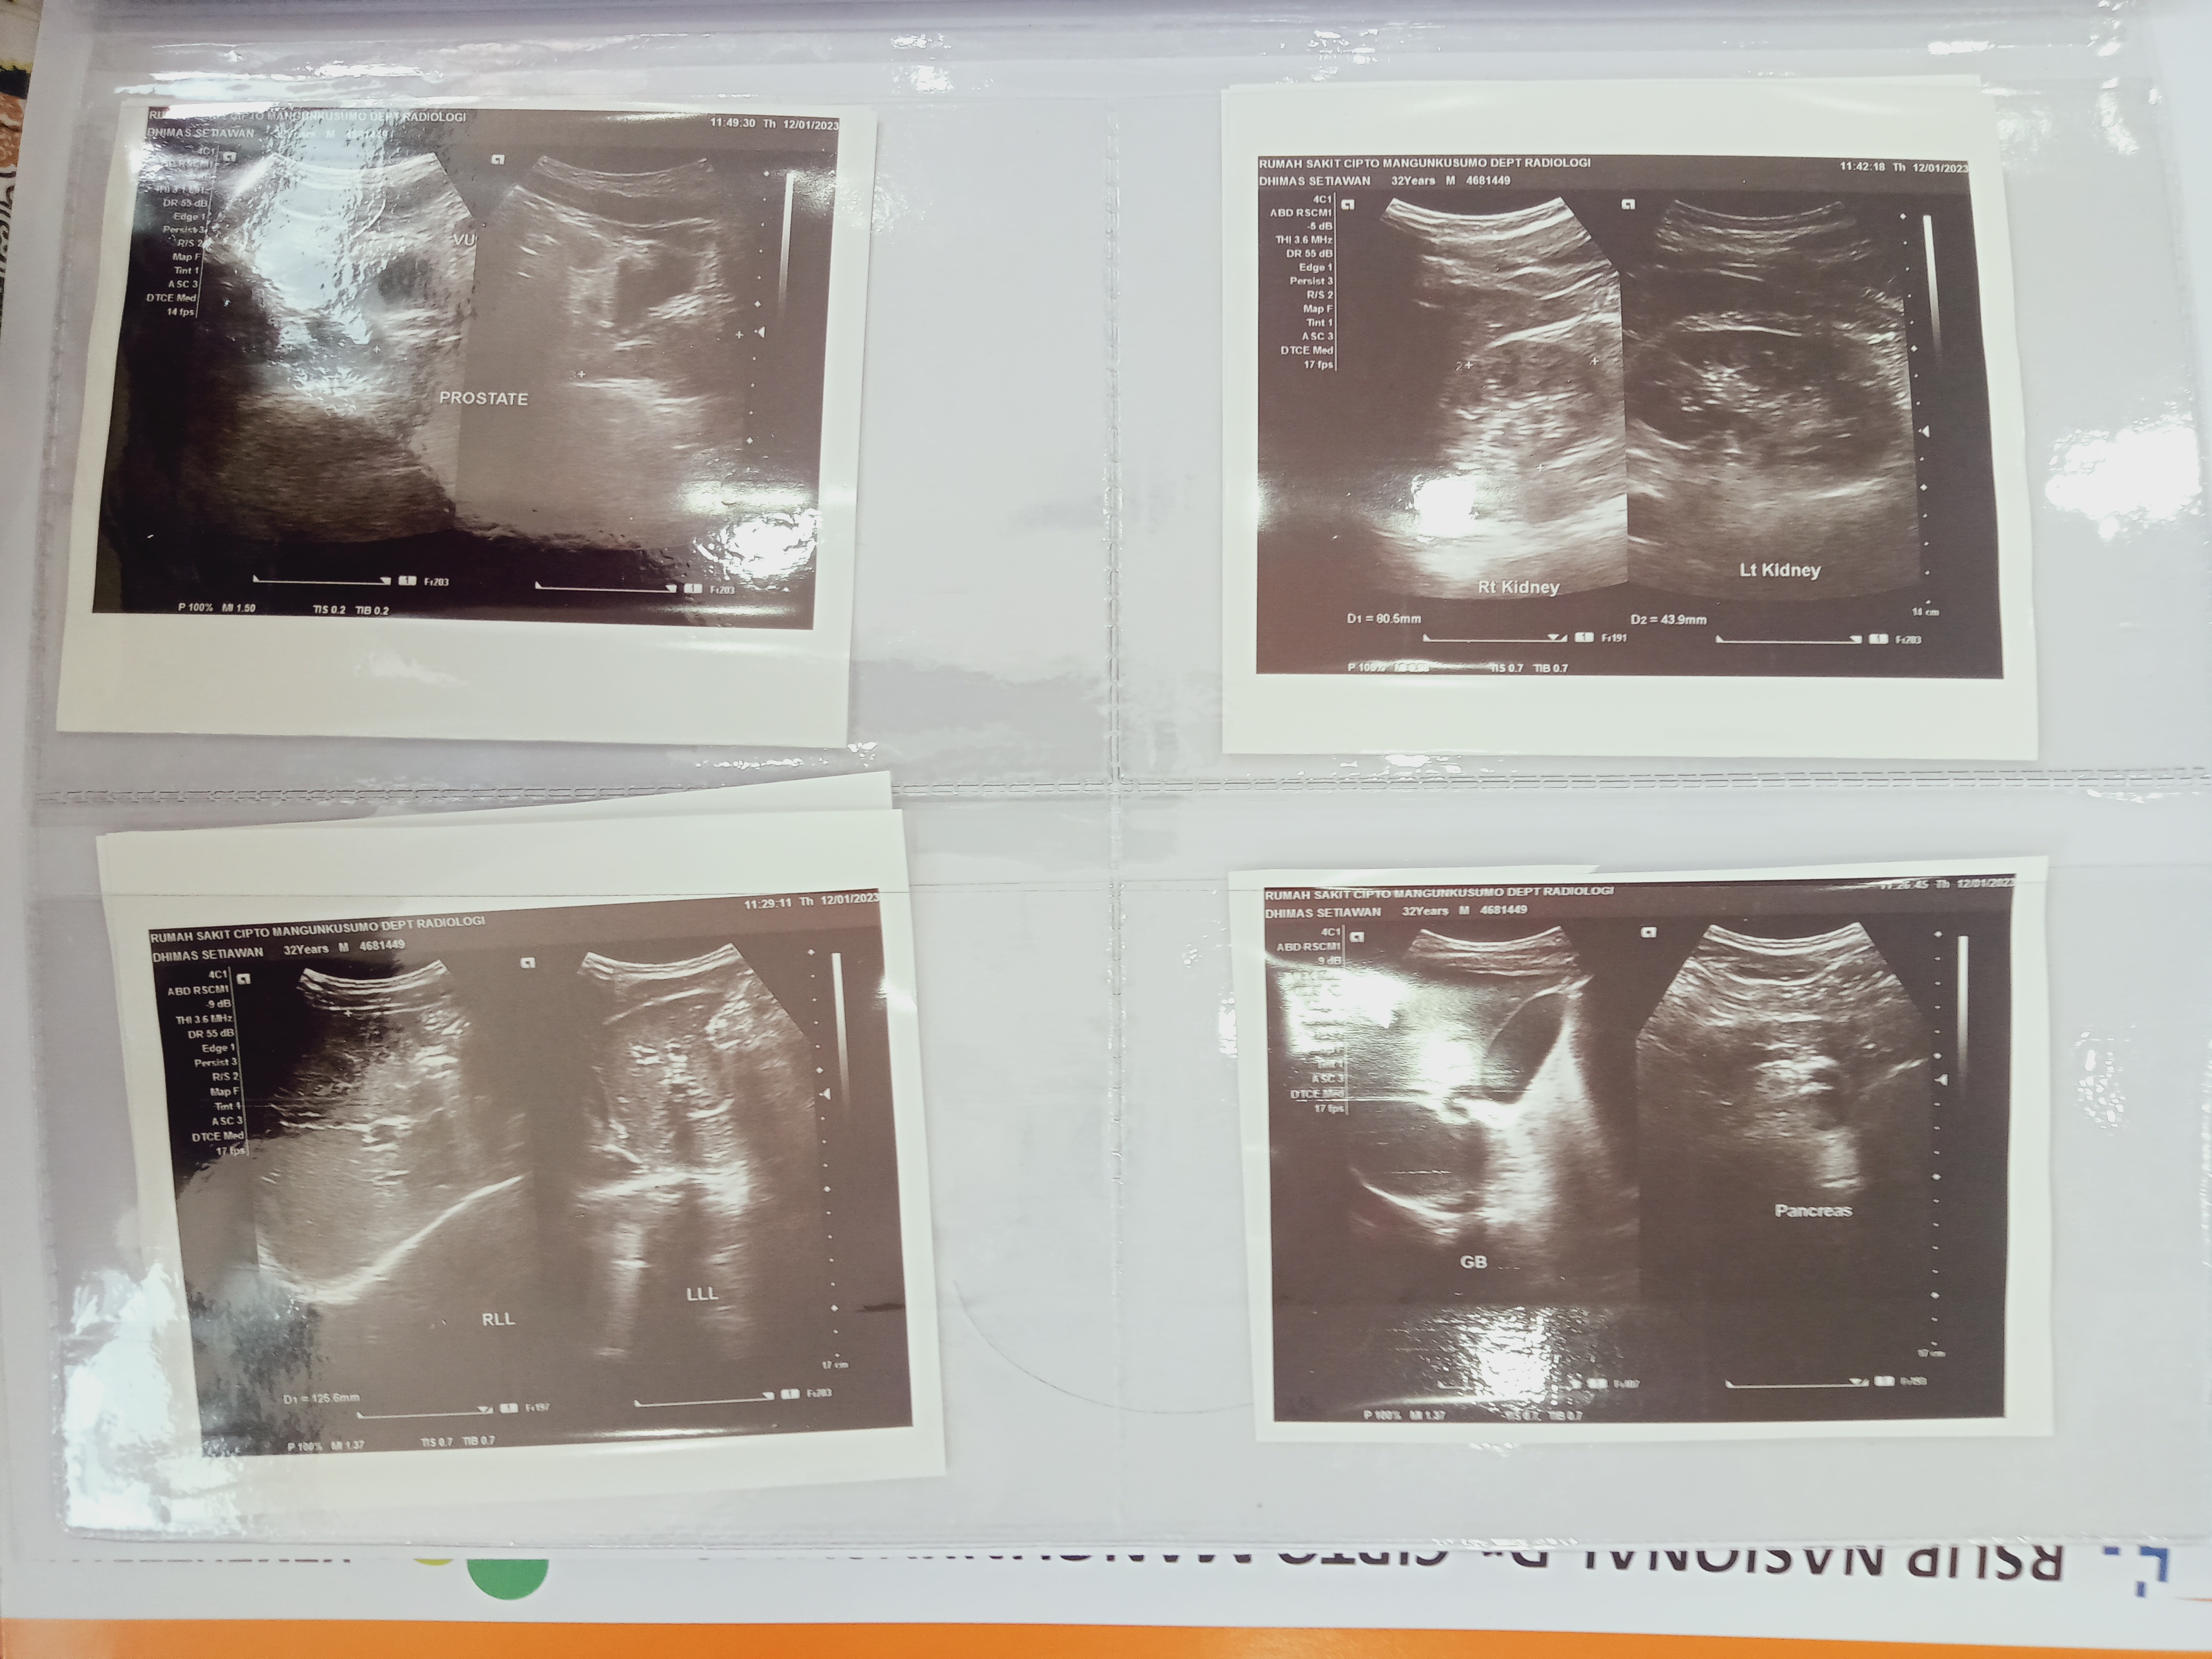

Hingga saat ini, Dhimas sudah genap satu bulan menjalani rangkaian pengobatan oleh tim dokter RSCM, cek lab, rontgen/USG dan pengambilan sampel (biopsi). Tindakan selanjutnya, akan dilakukan operasi dengan pembiusan total yang mana nantinya akan diangkat beberapa titik tumornya.